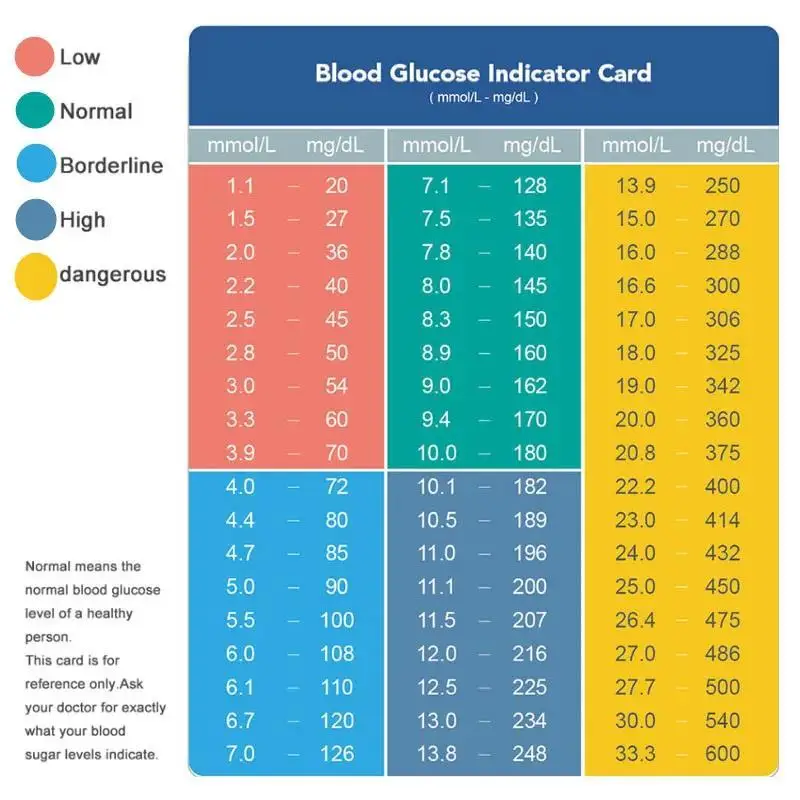

Units: mmol/L and mg/dl

Test range: 1.1-33.3 mmol/L (20-600mg/dl)